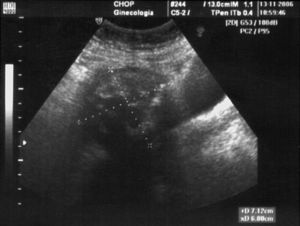

Caso clínicoPaciente de 44 años, a la que su médico de cabecera deriva a consultas externas de nuestro centro para revisión ginecológica correspondiente. Como único antecedente médico de interés relata apendicectomía hace 18 años en centro privado. Nuligesta. Eumenorreica. Índice de masa corporal 22. Refiere dolor inespecífico, de intensidad variable y larga evolución en el tiempo, que describe como “sensación de peso” localizado en hipogastrio y fosa ilíaca derecha, no en relación con los ciclos menstruales y acompañado de hábito intestinal estreñido. La especuloscopia describe un cérvix macroscópicamente normal y vagina correctamente epitelizada. En la exploración bimanual, se constata un útero discretamente aumentado de tamaño e irregular, fundamentalmente a expensas de canto derecho, de consistencia pétrea, escasamente desplazable. La ecografía vaginal informa de un útero lateralizado a la derecha, con ecoestructura y grosor endometrial normales, ambos ovarios normales, y una tumoración de 72×64mm, heterogénea, con áreas de aspecto calcificado en su interior (fig. 1) localizada en la zona de cuerno uterino derecho, cuya sombra acústica posterior dificulta su estudio detallado, y establece como primera posibilidad el diagnóstico de mioma pediculado. Se completa estudio con marcadores tumorales, que son negativos.